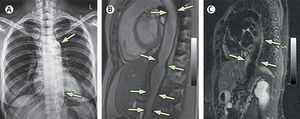

Recurrent chest pains A 40-year-old woman presented with complaints of a 4-year history of recurrent central chest pain. She gave a history of having a prolonged fever for about 3 months accompanied by arthralgia at the age of 13 years, but the fever resolved gradually. 1) Hyperparathyroidism 2) Idiopathic hypercalcaemia 3) Aortic aortitis 4) Hyperlipidaemia